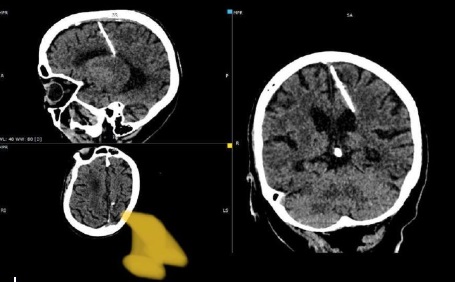

Szahalin város kórházában, CT-vizsgálat során vettek észre orosz orvosok egy három centi hosszú tűt egy most nyolcvan esztendős nő agyában. A tű nem sokkal születése után kerülhetett az agy lebenyébe – írja a HVG. A vizsgálat során készült képet a Telegramon osztották meg. Ezen az látszik, hogy bár a tű behatolt a parietális lebenybe,

a nő túlélte az esetet, mi több károsodást sem szenvedett.

Mivel máig nem jelentkezett semmilyen tünete de a tű eltávolítása komolyabb kockázattal járna, a kamcsatkai orvosok úgy határoztak, hogy a tű marad az idős hölgy fejében, nem műtik meg.